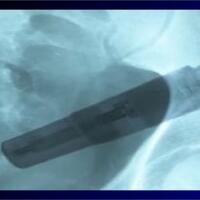

Kecelakaan Aneh, Vibrator Terjebak di Usus Besar